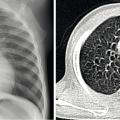

Une radio du thorax de face, en inspiration et expiration, est nécessaire lors du diagnostic. Sa normalité permet d’écarter une grande partie des autres pathologies mimant l’asthme.

En cas de doute, si les manifestations sont fréquentes et/ou sévères, il est indispensable d’élargir les explorations (endo-scopie bronchique, scanner thoracique, étude de la motilité ciliaire, bilan immunitaire, test de la sueur) en milieu spécialisé. La figure 1 illustre le cas d’un enfant qui après 3 bronchiolites a été considéré comme asthmatique. La persistance des symptômes malgré le traitement par corticoïdes inhalés a motivé un avis spécialisé : les explorations ont abouti à la découverte d’un double arc aortique (anomalie cardiaque fœtale responsable de compression trachéobronchique et/ou œsophagienne).